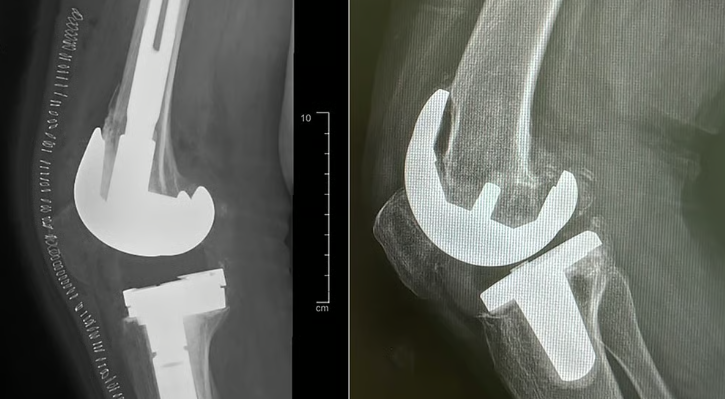

أجرى مستشفى الدكتور سليمان الحبيب الطبي بالخبر، عملية استبدال مفصل ركبة معقدة وناجحة، أنهت معاناة سيدة تبلغ من العمر “74” عاماً كانت قد خضعت لجراحة مماثلة بمستشفى آخر منذ نحو “18” عاماً، وعانت مؤخراً من حزمة واسعة من الأعراض الحادة، التي غيرت نمط حياتها.

وأوضح د. القحطاني أن الفريق الطبي أخضعها لفحوصات طبية دقيقة، أهمها الأشعة المقطعية لاختبار جودة العظام وكثافتها، والتأكد مما إذا كانت مصابة بالهشاشة أم لا، وغيرها من الفحوصات التي بينت وجود تخلخل وانحراف في المفصل، مع تآكل العظم، وتلف الغضاريف.

واستطرد د. القحطاني الحاصل على الزمالة الكندية للإصابات الرياضية وجراحة المناظير واستبدال المفاصل، قائلاً أن المراجعة أخضعت لعملية جراحية معقدة تم فيها استخراج المفصل الصناعي القديم، واستبداله بآخر نوعي مخصص لمثل هذه الحالات، كما تم وضع دعامات لتثبيت المفصل، مشيراً إلى أن العملية مضت بصورة سلسلة ووفقاً للخطة العلاجية، وتكللت ولله الحمد جهود الفريق الطبي بالنجاح، إذ عادت المريضة للمشي على قدميها بصورة طيبة بعد العملية مباشرة بمساعدة أخصائي العلاج الطبيعي، قبل أن تغادر المستشفى بعد أيام بحالة جيدة.